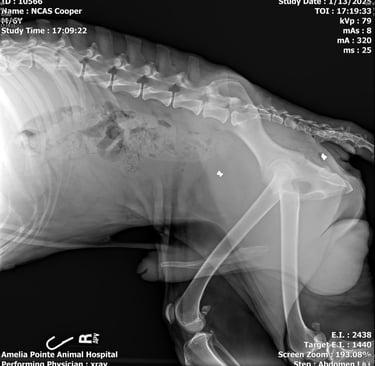

Cooper’s story is heartbreaking. He was found near the woods in Hilliard, painfully thin and carrying the scars of a cruel past. X-rays revealed he had been shot with BB guns, and four pellets are still lodged in his body.